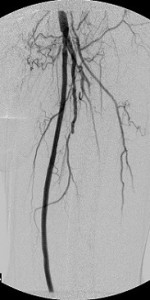

It was , therefore, helpful to the patient that I eliminate as much of the upstream disease as was feasible and dilate the critical stenosis of the left tibioperoneal trunk. Thus, balloon angioplasty was applied to the common femoral obstruction and the tibioperoneal trunk stenosis and a stent-graft was used to exclude from the circulation all the superficial femoral arterial disease. The bottom panel of images shows the immediate outcome of these interventions. The ulcer eventually healed.